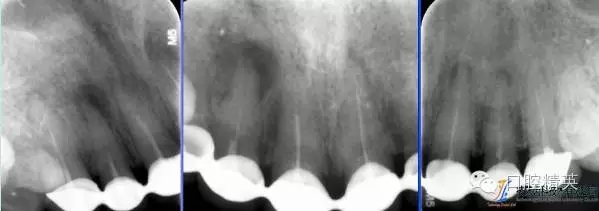

術(shù)前根尖片

術(shù)后根尖片